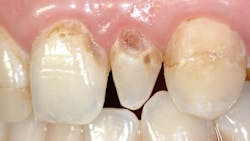

Current composites are not cariostatic and have microscopically open margins. They do not seal tooth preparations (figure 2).

Glass ionomers seal tooth preparations and are cariostatic (figures 3 and 4). But glass ionomers still have some limitations listed above.